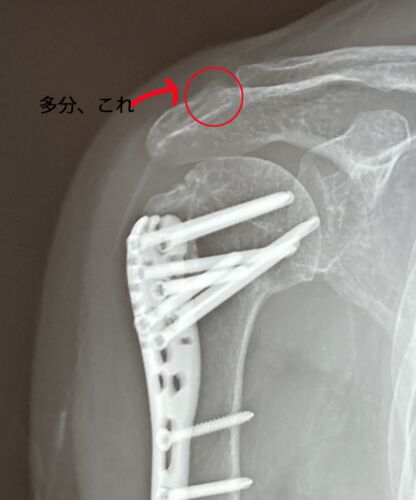

手術した総合病院での最後の診察。あー-、上腕骨近位端骨折ロス。プレート、外すことも出来たらしいけれど、結局、外さないことに・・・(完)

【上腕骨近位端骨折】もくじ 骨の突起 肩がコキコキなる プレートを外す手術について 術後1年のレントゲン写真・CT写真 昨日は、4か月ぶりの執刀した総合病院での診察でした。 今回は、 レントゲン撮影 CT撮影 診察 です。 去年の3月末にスケート教室で転倒…